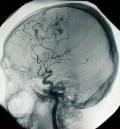

La enfermedad cerebrovascular o ictus es la primera causa de discapacidad y la segunda causa de demencia después del Alzheimer